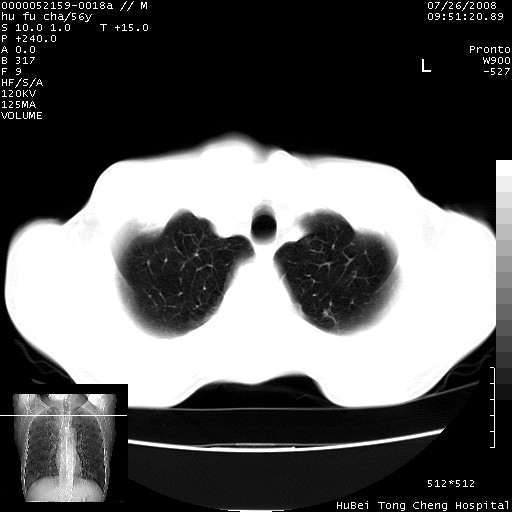

以下是引用zsl6918在2008-8-25 22:47:00的发言:[br]胸骨,胸椎及肋骨均可见多发转移表现,肝内低密度结节不除外转移。原发灶可能在右肺。双侧可见支扩表现。

以下是引用卜一在2008-8-26 8:02:00的发言:[br][br] 支持:肺癌并肺内,胸骨,胁骨,胸椎及肝内转移!另:左肺支气管扩张征伴感染! [br]

以下是引用zjzjr在2008-8-26 11:03:00的发言:[br]支持:肺癌并肺内,胸骨,胁骨,胸椎及肝内转移!另:左肺支气管扩张征伴感染!